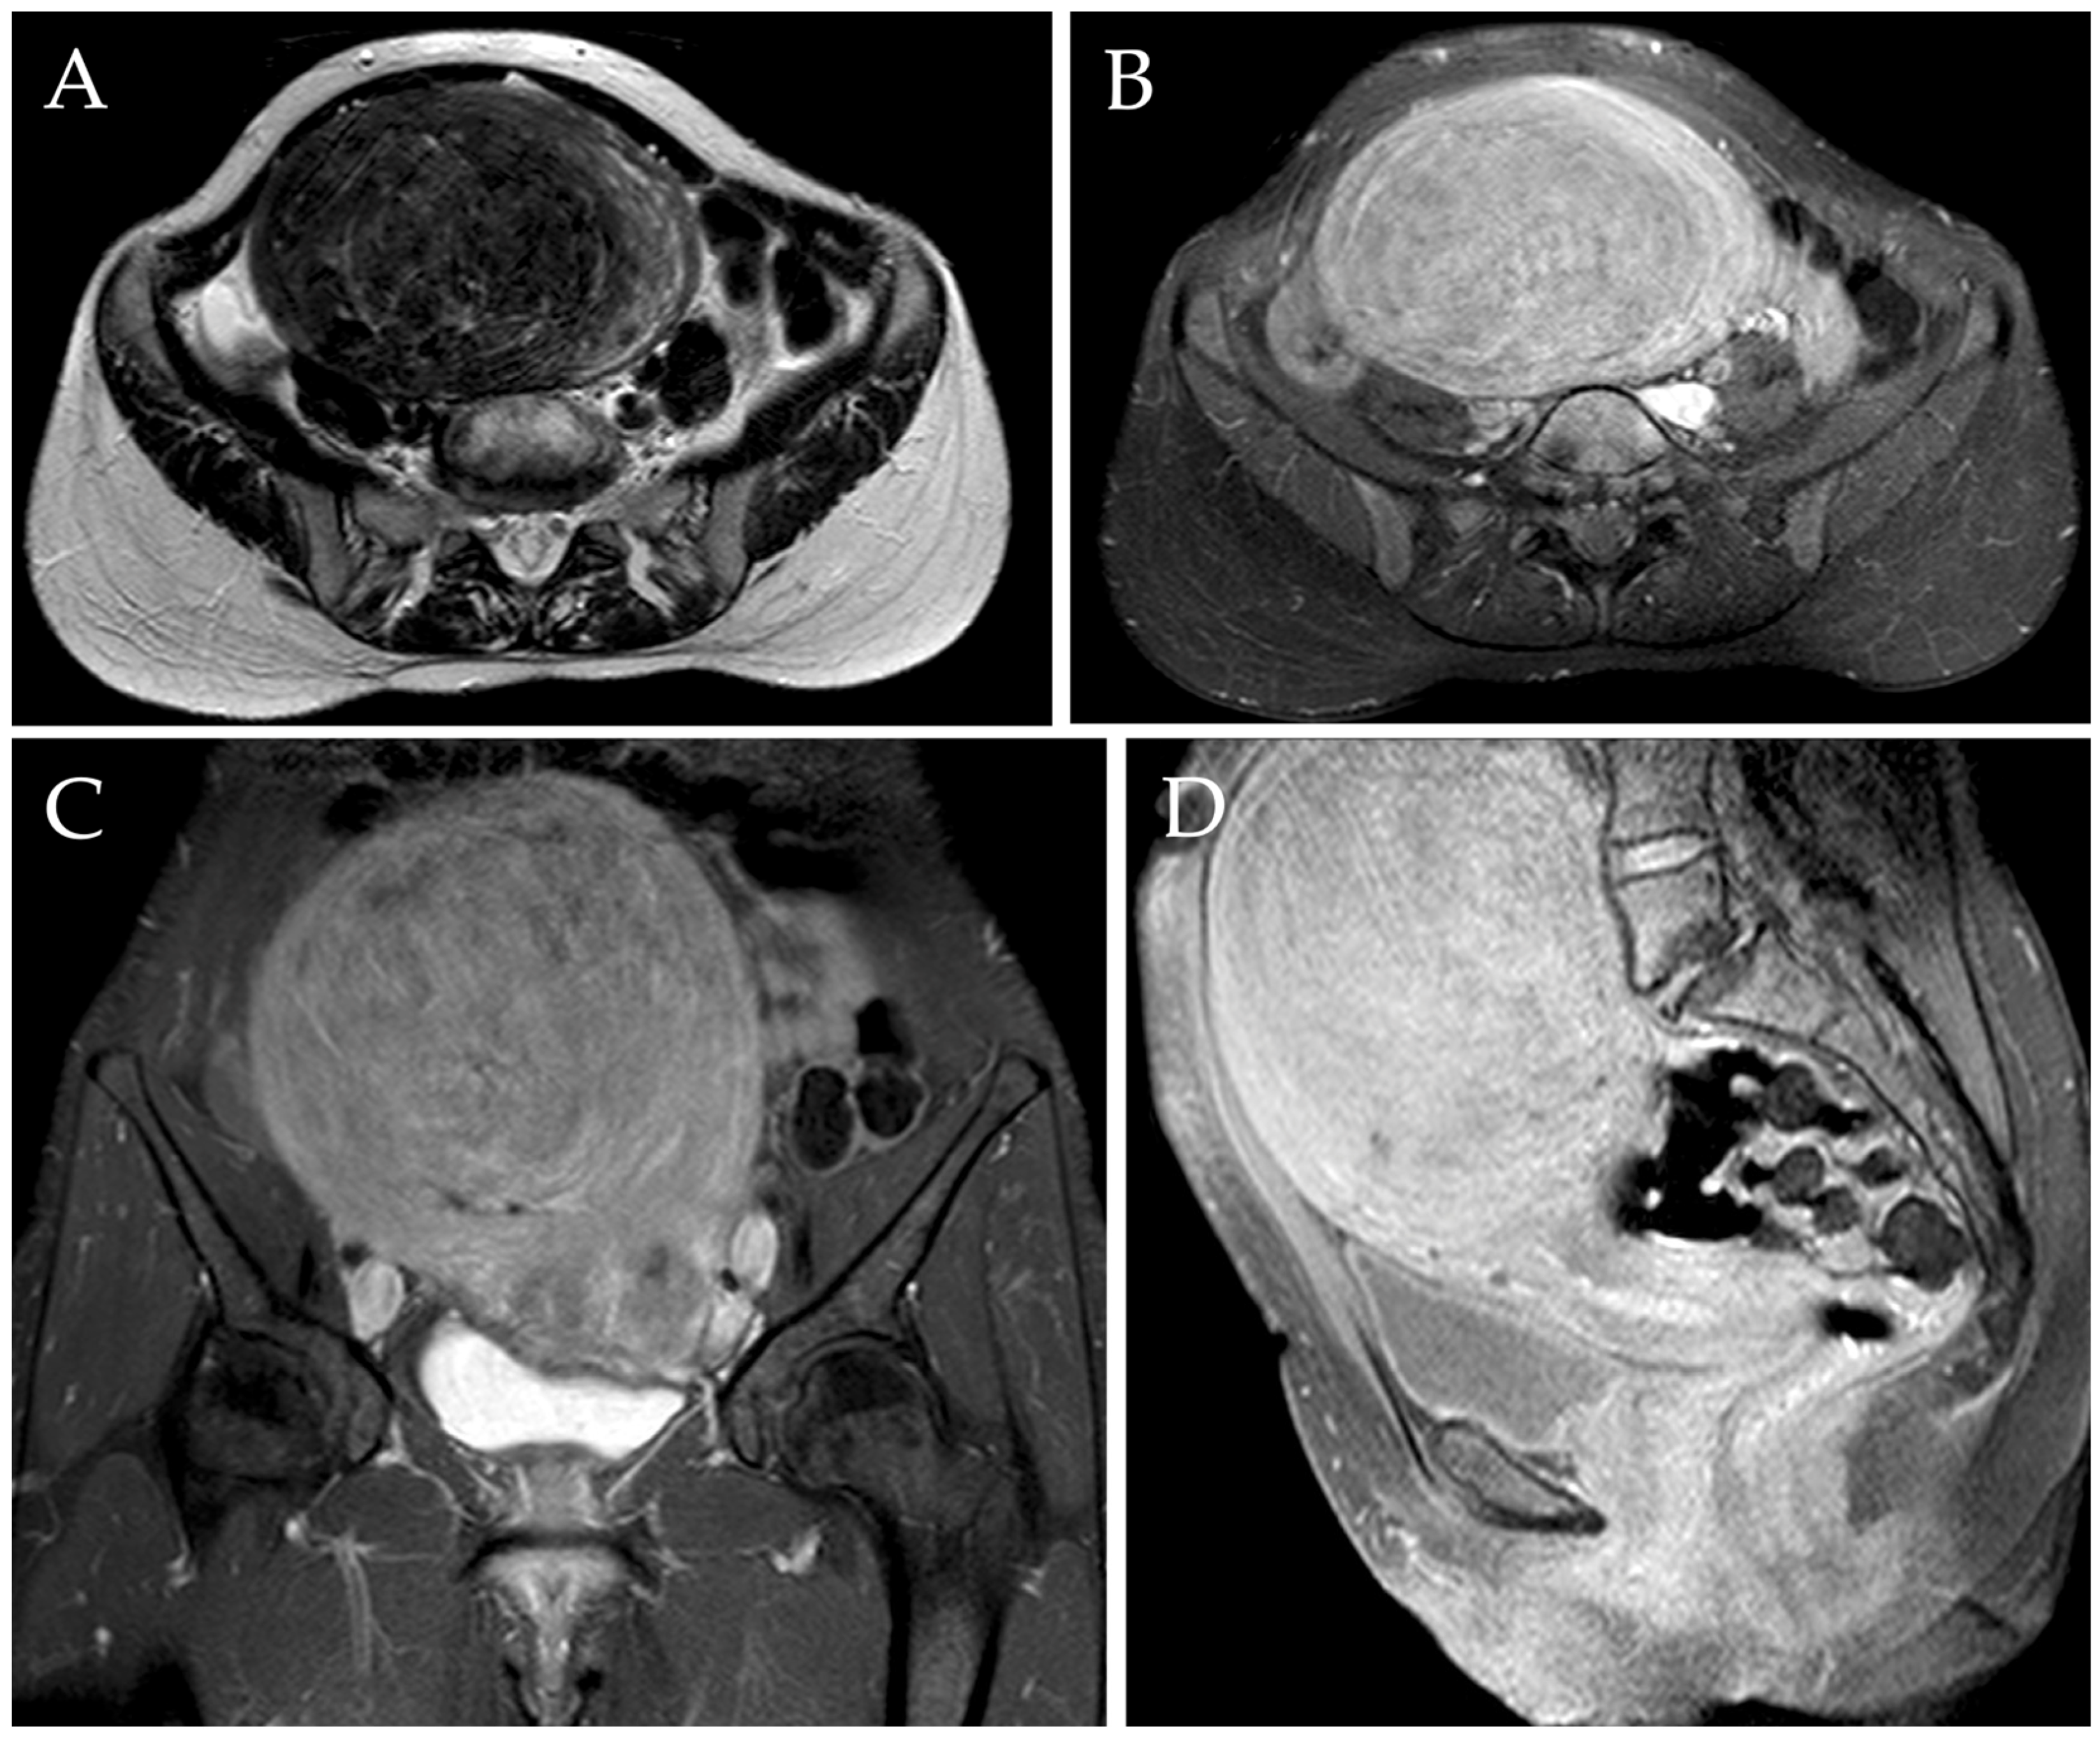

Radiological evaluation of the myomas was assessed through TV-US or MRI independently by two radiologists with 3 and 10 years of experience in the field, both before the procedure (Figure 2) and after 1 year. MRI scans were performed using the same 1.5T MRI superconductive scanner (HDX-t Signa; General Electric®, Milwaukee, WI, USA). Pelvic MR scans included pre-contrast axial T1-w images, pre-contrast axial, sagittal, and coronal fat-saturated T1-w images, axial and sagittal T2-w images, axial diffusion-weighted images (DWI), and axial, sagittal, and coronal fat-saturated T1-w images after intravenous administration of gadolinium-based contrast agent (0.1–0.2 mmol/kg; Gadovist ®, Bayer-Schering Pharma, Berlin, Germany) [7,53].

Figure 2.

MRI of a 46-year-old woman complaining of metrorrhagia and pelvic pressure. Axial T2-w image (A) demonstrated the presence of a voluminous myoma localized in the fundal region, measuring approximately 140 mm. Axial, sagittal, and coronal post-contrast T1-w images with fat saturation demonstrated the typical enhancement of the mass (B–D).